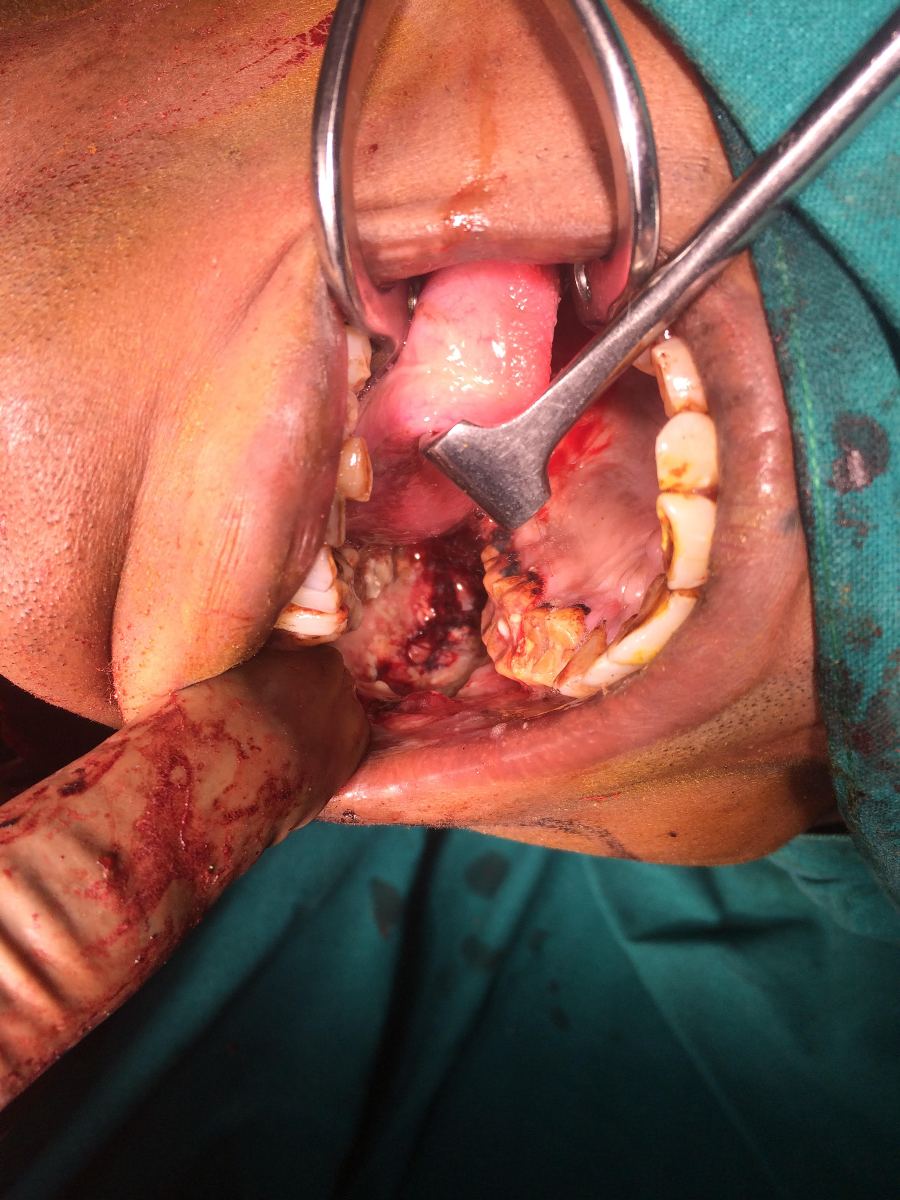

42 yrs old male suffering from right buccal mucosa carcinoma involving upper and lower GB sulcus .right radical neck dissection with right distal mandibulectomy with right upper alveolectomy with right PM flape done.